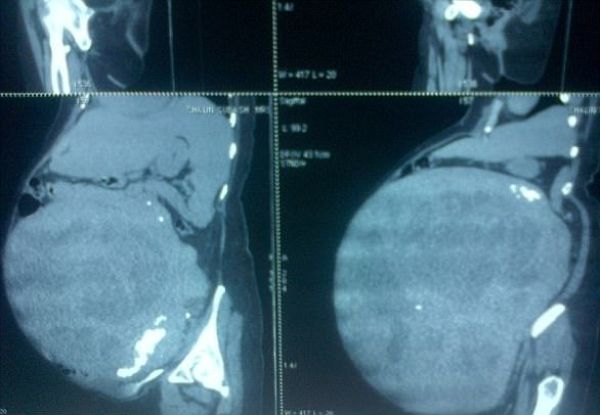

gif_animation グアテマラにて、40歳の女性の体の中でおよそ7年間成長し続けた「子宮筋腫(子宮内の良性腫瘍)」のギャラリー。その重さ32kg。世界最大級だそう。[6]img